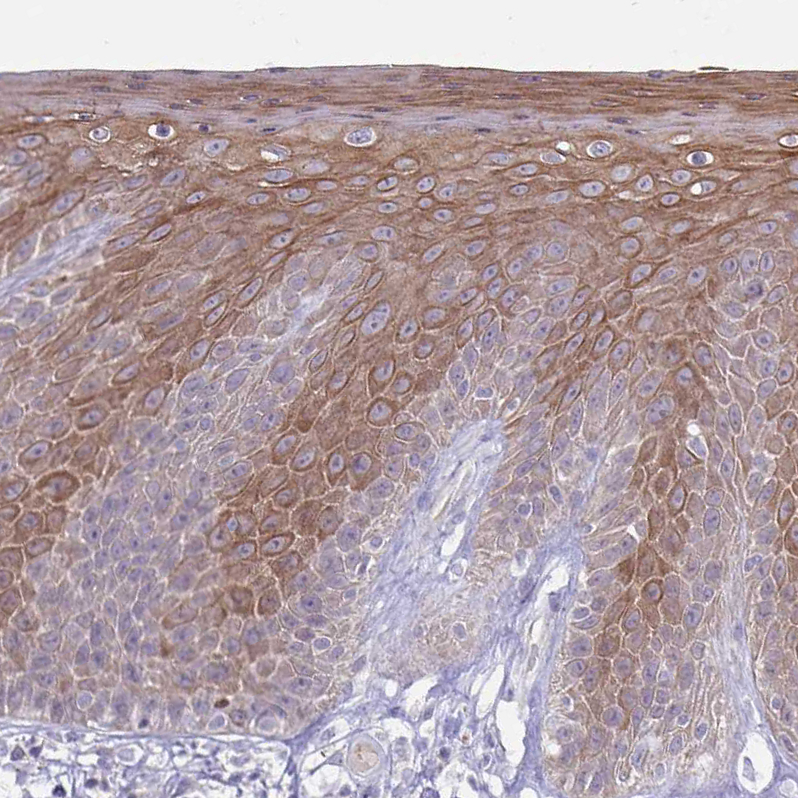

Immunohistochemical staining of human skin shows moderate cytoplasmic positivity in squamous epithelial cells.